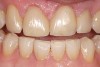

Next is the flexure risk assessment. Each tooth and existing restoration is evaluated for signs of past overt tooth flexure. Signs of excessive tooth flexure can be excessive enamel crazing (Figure 2), tooth and restoration wear, tooth and restoration fracture, microleakage at restoration margins, recession, and abfraction lesions. Often, the etiology is multifactorial and controversial. However, if several of these conditions exist, there is an increased risk of flexure on the restorations that are placed, which may overload weaker materials. Evaluation of this possibility is also based on the amount of remaining tooth structure. The more intact the enamel is, the less potential for flexure. The amount of tooth preparation can directly affect tooth flexure and stress concentration. There is much potential subjectivity in any observational assessment of clinical conditions; however, an assessment of flexure potential for each tooth to be restored is needed. A subjective assignment of Low, Medium, or High Risk for flexure is based on the evaluated parameters, as outlined below.

Figure 2  Image demonstrating excessive enamel crazing, leakage, and staining. Flexure, tensile, and shear risks would be medium to high. The substrate would depend on preparation.

Figure 2